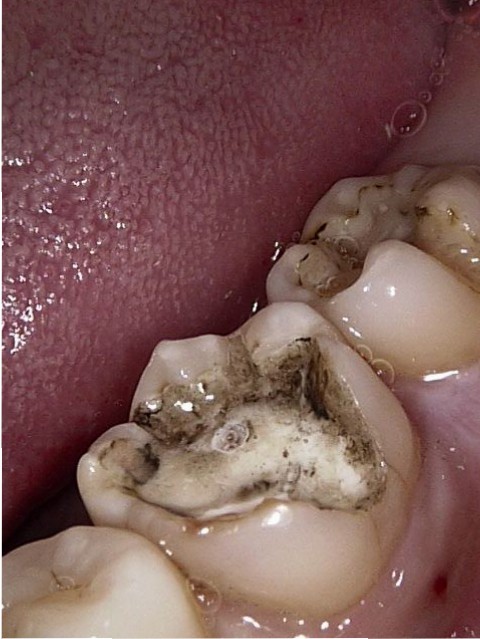

1_2017.03.26_L052